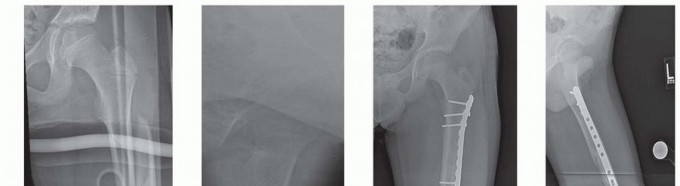

Chapter 22 Pediatric Hip Fractures Ernest L. Sink Benjamin F. Ricciardi DEFINITION Pediatric hip fractures co…